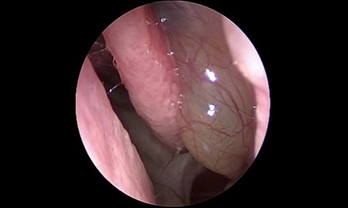

- Phát hiện sớm các trường hợp polyp mũi xoang, ung thư vòm họng qua nội soi.

Phẫu thuật nội soi chức năng xoang (Functional Endoscopic Sinus Surgery-FESS) giúp trả lại hệ thống xoang thông thoáng với kỹ thuật không đặt bấc mũi.

- Phẫu thuật nội soi mũi xoang với hệ thống định vị trong lúc mổ (Navigation) cho phép bác sĩ tiếp cận trực tiếp đến các vùng mũi xoang bị viêm, gia tăng khả năng quan sát các mốc giải phẫu trong hốc mũi để đánh giá một cách chính xác các bệnh lý sâu trong hốc mũi.

- Trên cơ sở đó, bác sĩ có thể dễ dàng thao tác loại bỏ sạch các tác nhân gây viêm và mủ mà vẫn bảo tồn tối đa niêm mạc lành và hạn chế nạo bỏ niêm mạc triệt để, tối ưu lưu thông không khí trong hệ thống xoang.